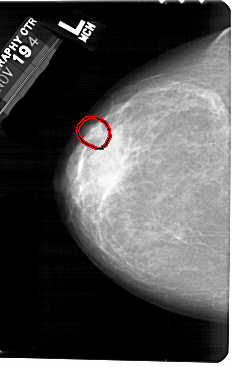

A_1556_1.LEFT_CC

FILE: A_1556_1.LEFT_CC.OVERLAY

TOTAL_ABNORMALITIES 1

ABNORMALITY 1

LESION_TYPE MASS SHAPE OVAL MARGINS OBSCURED

ASSESSMENT 4

SUBTLETY 2

PATHOLOGY BENIGN

TOTAL_OUTLINES 1

BOUNDARY